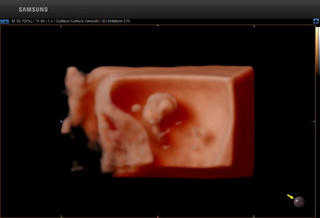

↓↓正常面部 ↓↓唇裂畸形